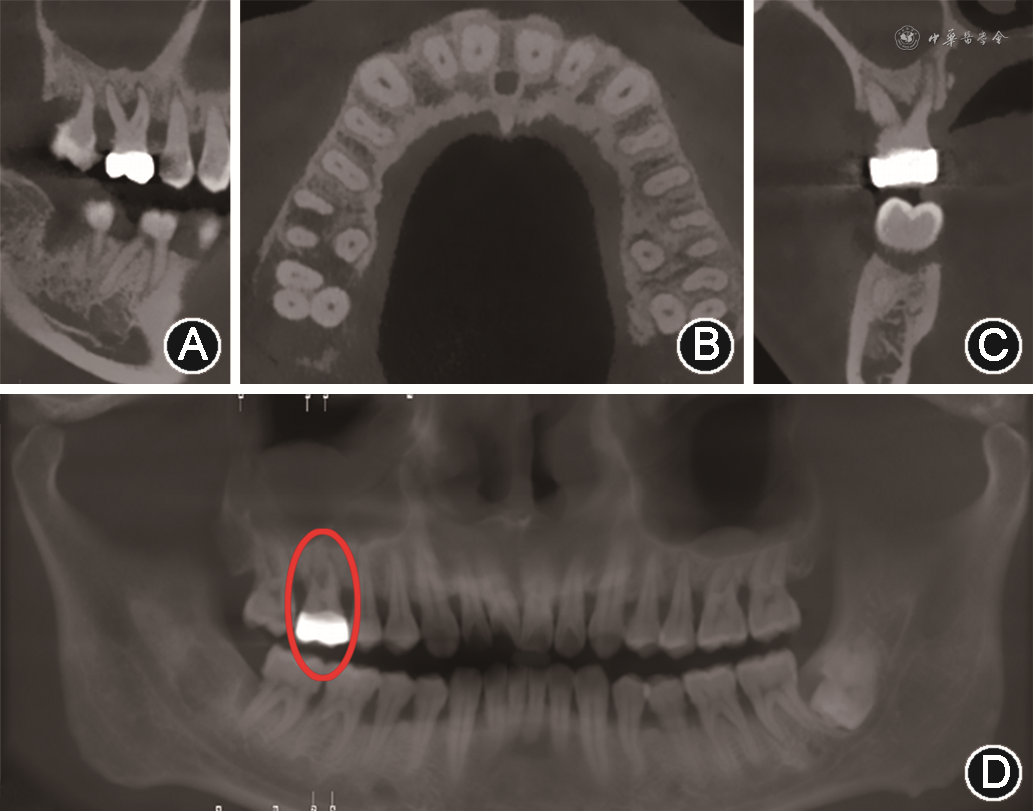

根分叉病变的诊断主要根据探诊和影像学检查。由于根分叉区的解剖结构特点,临床医师需使用特殊弯曲的根分叉探针——Nabers探针进行临床探诊。探诊时将Nabers探针置于根分叉入口冠方牙面上,再将探针以Z字形向根方移动,若探针可探及根分叉凹陷处,则为检测到根分叉病变(图1)。影像学诊断中,X线片对诊断根分叉病变有较大意义(图2),但二维影像学技术受投射角度及组织影像重叠影响,仅可提示根分叉病变的存在可能,必要时需借助锥形束CT进一步完善影像学检查[12, 13](图3)。

此外,牙髓感染、牙根折裂等潜在问题也需在检查根分叉病变时予以关注。由于牙本质小管、侧副根管等结构的存在,牙髓组织和牙周组织在健康、功能和疾病方面相互影响。根分叉病变临床诊疗管理时不能忽视患牙潜在的牙髓问题。这对患牙的疗效预测和治疗方案设计有重要意义。牙根折裂可导致局部牙槽骨快速丧失,当牙根折裂发生于根分叉区附近的根面时,可直接导致根分叉病变。临床需对单个牙位的牙槽骨大量破坏时刻保持警惕,锥形束CT等影像学检查可辅助早期诊断,减少患者的治疗时间和经济负担。